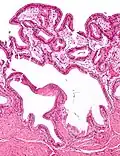

Micrografia da colesterolose da vesícula biliar. Mancha de H&E.

Na patologia cirúrgica, vesícula biliar de morango, mais formalmente colesterolose da vesícula biliar e colesterolose de vesícula biliar, é uma alteração na parede da vesícula biliar devido ao excesso de colesterol.[1]

O nome vesícula biliar de morango vem da aparência tipicamente pontilhada da superfície da mucosa, em um exame grosseiro, que se assemelha à aparência de um morango.